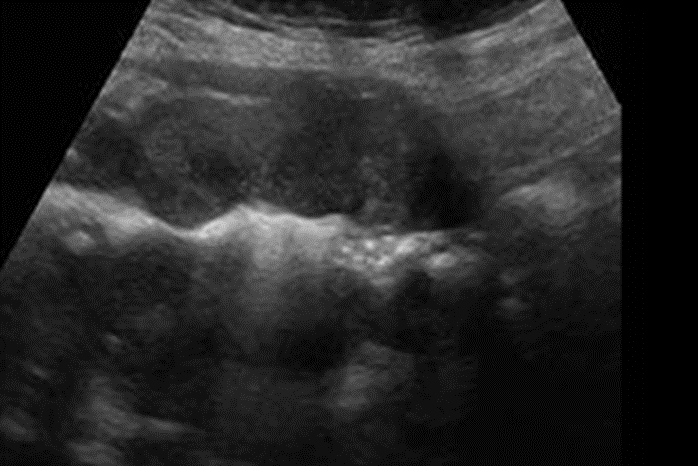

En Flanco izq en región de dolor, en relación a colon descendente, marcado engrosamiento de aspecto nodular, hipoecogénico y heterogéneo con moderada hiperemia al Doppler color y power. En signo de pseudoriñon, con leve aumento de la ecogenicidad de la grasa adyacente. Hallazgos sugerentes de adenocarcinoma

Se explora dirigidamente flanco izquierdo, donde en correspondencia con área de sensibilidad al paso del transductor, se identifica engrosamiento focal de la pared del colon descendente, con aumento de la vascularización al Doppler Color. Se esboza imagen de pseudoriñon, con aumento de la ecogenicidad de la grasa circundante.

• Lesión nodular de ecoestructura heterogénea.

• Con ecogenicidad variable:  Hipo-hiperecogénica.

• Perdida de la estratificación de la mucosa intestinal.

• Signos de Pseudo Riñón: Los gases simulan ser el seno renal y el tumor el parénquima renal.